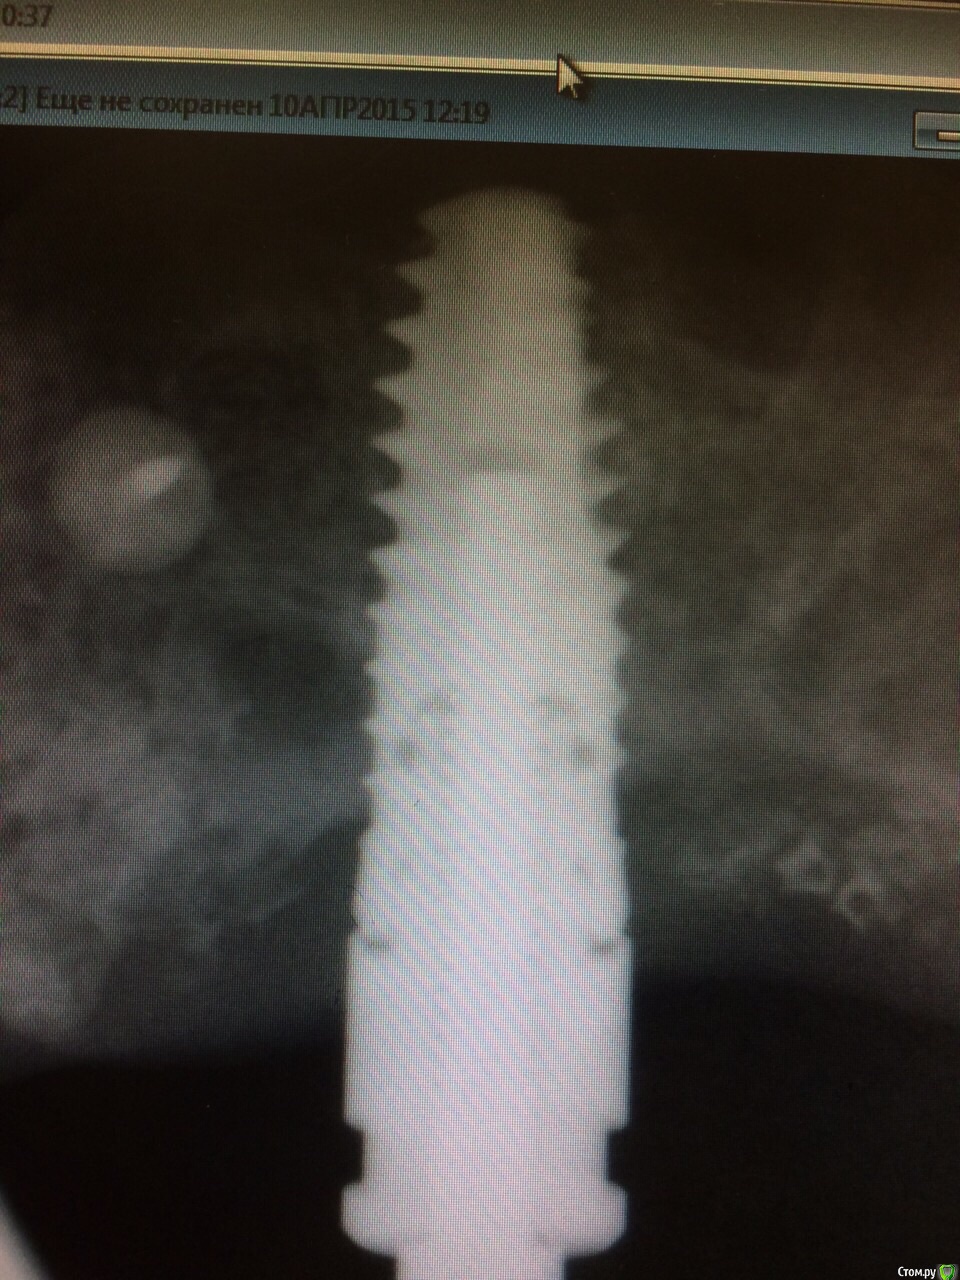

Mbegiev Опубликовано 31 марта, 2015 Поделиться Опубликовано 31 марта, 2015 У/з пробовал , что еще можно ? Не удаляя имплантат))Система xive Ссылка на комментарий

Mbegiev Опубликовано 31 марта, 2015 Автор Поделиться Опубликовано 31 марта, 2015 От ортопеда вернулся таким) говорит не шел по резьбе решил под нагрузкой.. Ссылка на комментарий

gum Опубликовано 15 апреля, 2015 Поделиться Опубликовано 15 апреля, 2015 Несколько раз такое было именно на xive наверное на металле экономили , всегда без проблем винт доставал ультразвуком Ссылка на комментарий

Mbegiev Опубликовано 16 апреля, 2015 Автор Поделиться Опубликовано 16 апреля, 2015 Закончилось все хорошо! Мы его победили) Набор для извлечения и нарезки новой резьбы нам помог. 2 Ссылка на комментарий